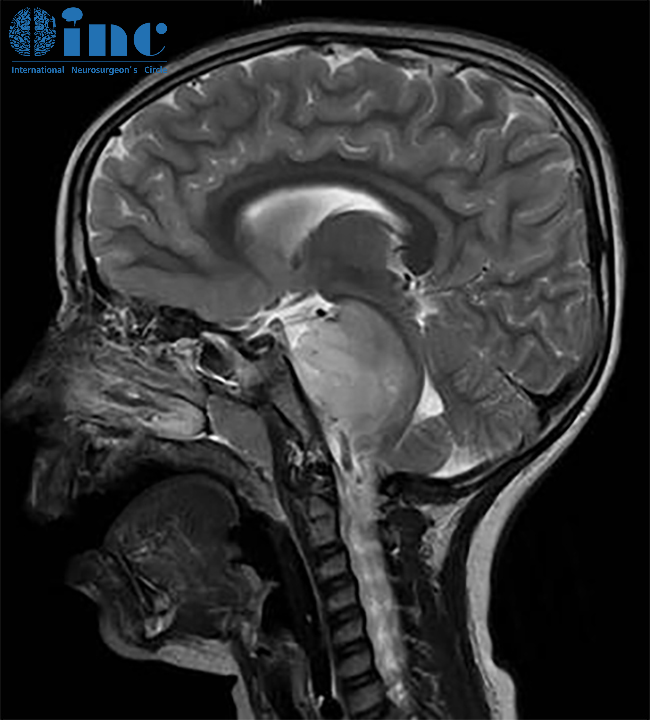

示范手术中,巴教授就建议一名21岁脑干中脑顶盖胶质瘤患者尽早手术。肿瘤直径从8mm长到18mm,两月内竟激增6mm!迅速增长的肿瘤,让一家人陷入恐慌,必须尽快找到能为孩子安全手术的主刀医生。巴教授:这个中脑肿瘤是有明确的手术切除指征,尤其在最近一段时间内肿瘤尺寸不断增大。长时间等待只会给肿瘤更多的生长机会,并对脑干产生危险,从而(加重)影响患者的临床状态。